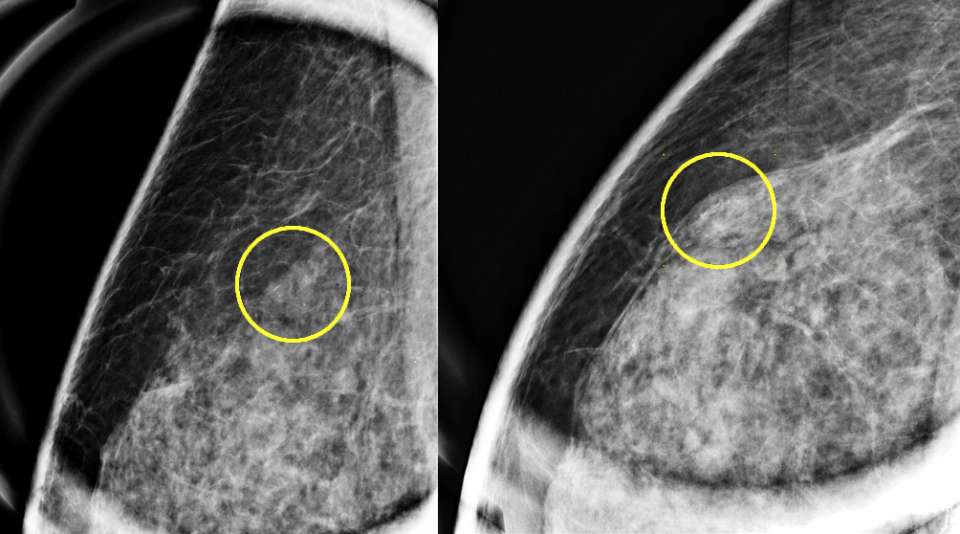

Case: Flat Epithelial Atypia Figure 1

Magnification mammographic images demonstrating grouped, amorphous calcifications, with subsequent biopsy demonstrating FEA